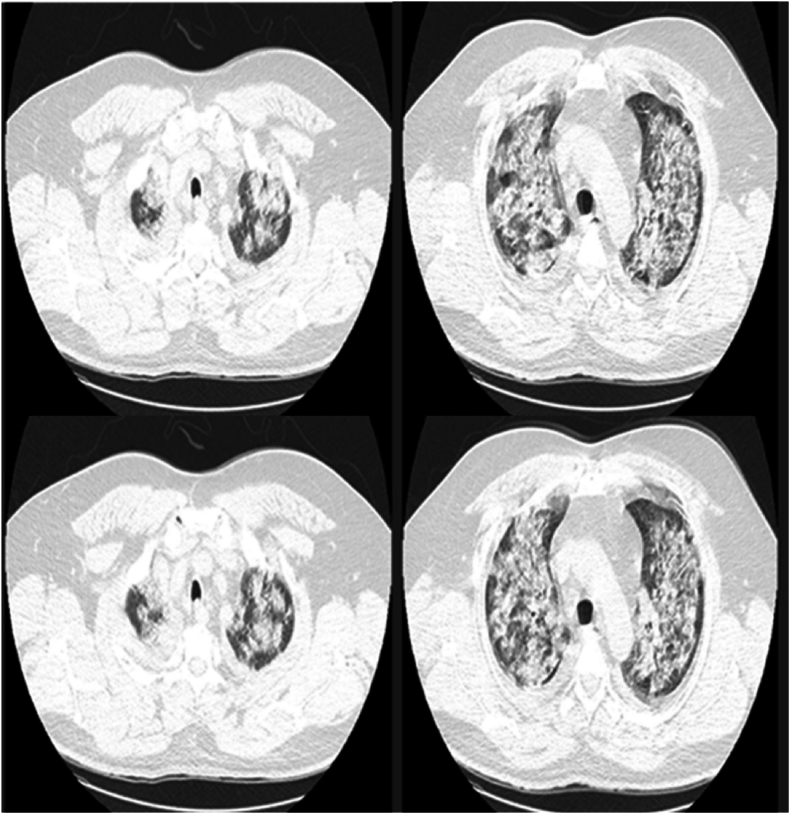

一名COVID-19患者的汉坦病毒肺综合征,玻利维亚,2022年。

Hantavirus pulmonary syndrome in a COVID-19 patient, Bolivia, 2022